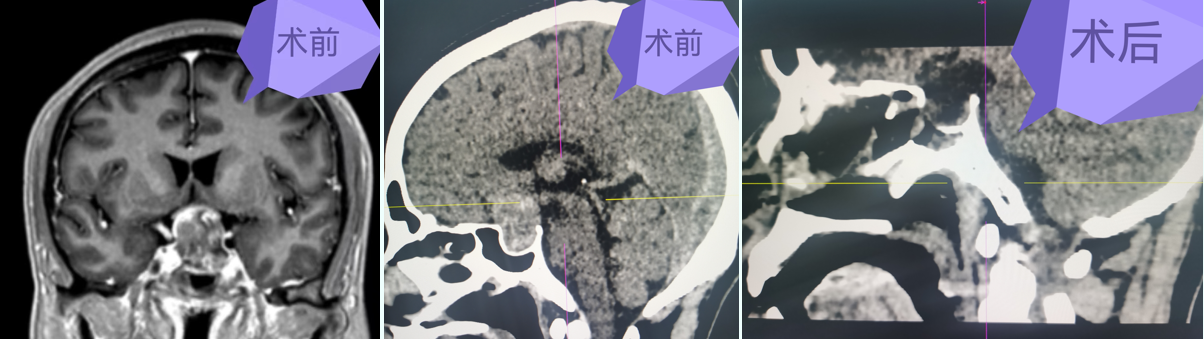

图片 7.png

挑战生命禁区,颅底、侧颅底占位微创切除术

从Ommaya囊侧脑室置入术到大脑半球、小脑半球占位切除术,从垂体瘤到颅底、侧颅底等复杂颅内占位切除术,凭借先进的微创技术与高精尖的设备,为众多患者解除了病痛,让患者重新找回了生活的精彩。

目前,肿瘤医院能熟练开展神经导航引导下、显微镜及神经内镜微创手术治疗各种神经肿瘤(脑膜瘤、胶质瘤、垂体瘤、听神经瘤、脑转移瘤、脑室系统肿瘤等);微型机器人引导下深部及重要功能区脑组织病变活检术;脑血管病(高血压脑出血、血管畸形、动脉瘤、烟雾病)及颅脑损伤手术;各种类型脑积水的分流手术;面肌痉挛、三叉神经痛、痉挛型脑瘫、帕金森、脑梗死的诊治;脑脓肿、椎管内感染等各种复杂的颅内感染性疾病的综合治疗;去骨瓣减压术后钛网或PEEK材料颅骨修补术;频发型癫痫的迷走神经刺激术(VNS);癌痛、昏迷促醒治疗等。